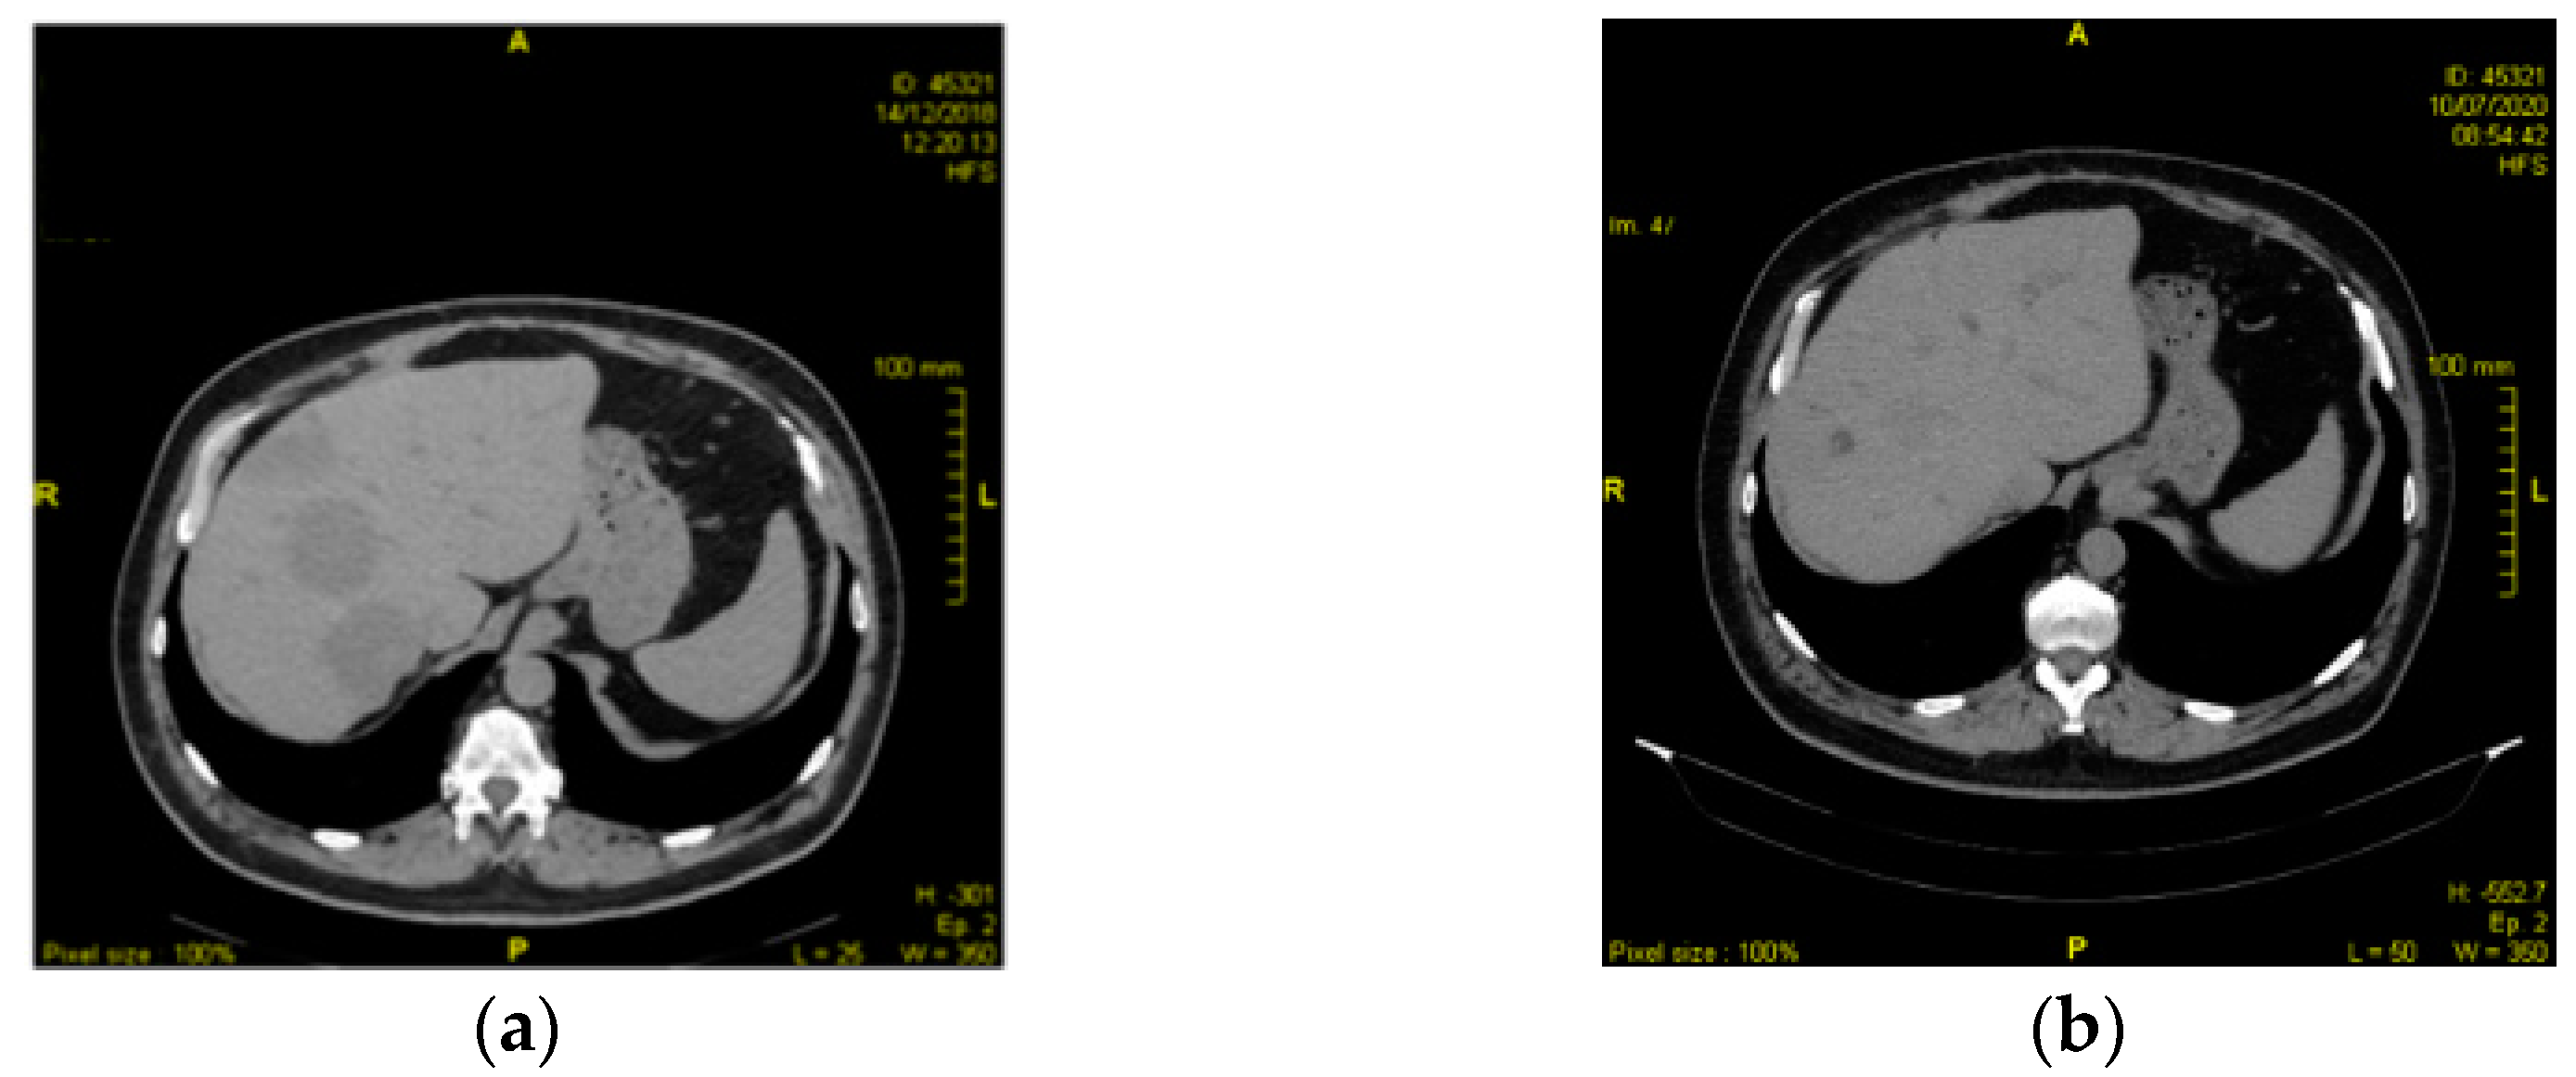

2.1. Case 1

2.2. Case 2